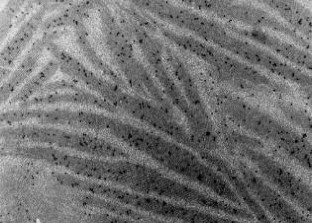

Die Lupusnephritis ist ein bekanntes Phänomen beim systemischen Lupus erythematodes (SLE). Wir untersuchten die Nierenbiopsie einer 30-jährigen Frau mit SLE. Die Anamnese zeigte einen klinisch typischen SLE mit generalisierten Symptomen mit positivem ANA- und Anti-ds-DNA-Titer ohne Nachweis von Lupuskoagulans, des Rheumafaktors, von Kryoglobulinen sowie ohne Antiphospholipid-Antikörper. Eine Paraproteinämie war weder für IgG noch für IgA oder IgM nachzuweisen. Mit Hilfe der Lichtmikroskopie, der Elektronenmikroskopie sowie der Immunelektronenmikroskopie wurden elektronendichte Ablagerungen in subepithelialer, subendothelialer und mesangialer Lokalisation nachgewiesen. Zusätzlich fanden wir sowohl in den elektronendichten Ablagerungen, als auch im angrenzenden Mesangium Kristalle eines elektronendichten Materials. Diese kristallinen Strukturen sind aus IgG und κ-Leichtketten zusammengesetzt, während IgM, IgA sowie λ-Leichtketten mittels Immunelektronenmikroskopie nicht nachzuweisen waren.

Lupus nephritis is a common phenomenon in Systemic Lupus Erythematosus (SLE). We analyzed a renal biopsy of a 30-year-old woman with SLE. The clinical history showed a typical SLE with generalized symptoms without demonstrable lupus coagulant, positive for anti-nuclear antibodies and anti-ds-DNA antibodies but negative for rheumatoid factor, cryoglobulins and antiphospholipid antibodies. A paraproteinemia for IgA, IgG and IgM was not detectable. Using light, electron and immunoelectron microscopy electron-dense deposits were noted in subepithelial, subendothelial and mesangial position. Most remarkably, the electron-dense deposits and mesangial areas in the vicinity of deposits contained an electron-dense crystalline material. The crystalline structures were composed of IgG and kappa light chains, while they were negative for IgM, IgA and lambda light chains, as demonstrated by immunoelectron microscopy.

Abb. 4.